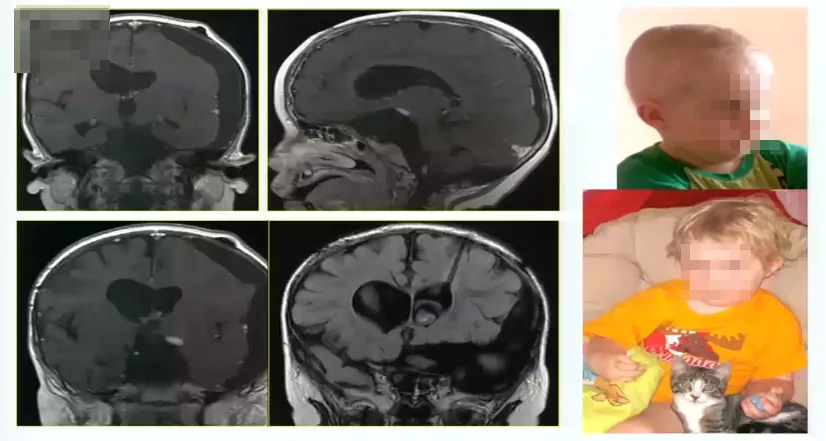

手术病例5:

11岁,3个月大时出现首次症状(拒绝喂养),7岁时出现性早熟和过度疲劳。10岁时经翼点入路部分切除肿瘤,诊断为毛细胞性星形细胞瘤。第二次经蝶手术进行囊肿抽吸,然后用卡铂化疗,无局灶性神经损伤。肿瘤仍有残余,孩子父母便寻求巴特朗菲教授的治疗,最终巴教授和dirocco教授共同为其手术。

术中情况:前纵裂入路全切肿瘤,下图为术中核磁检查。

术后情况:术后出现并发症,血钠下降非常厉害,术后一周还出现癫痫大发作。通过内科治疗,逐渐恢复。因此巴特朗菲教授表示一定要注意病人术后血钠水平和激素水平的变化。